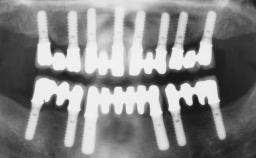

The 1-year follow-up radiographs demonstrate successful sinus floor elevation and stable bone crest levels around both implants, leading to a favorable long-term prognosis of the implant-supported prosthesis.